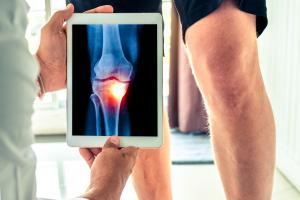

Actualité publiée le 17/03/2022ARTHROSE du GENOU : Sur l'excès d'injections d’acide hyaluronique

Actualité publiée le 14/02/2022